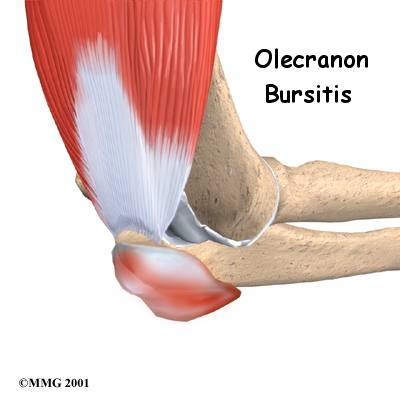

A bursa is a sac made of thin, slippery tissue. Bursae occur in the body wherever skin, muscles, or tendons need to slide over bone. Bursae are lubricated with a small amount of fluid inside that helps reduce friction from the sliding parts.

The olecranon bursa is located between the tip, or point, of the elbow (called the olecranon) and the overlying skin. This bursa allows the elbow to bend and straighten freely underneath the skin.

Olecranon Bursa